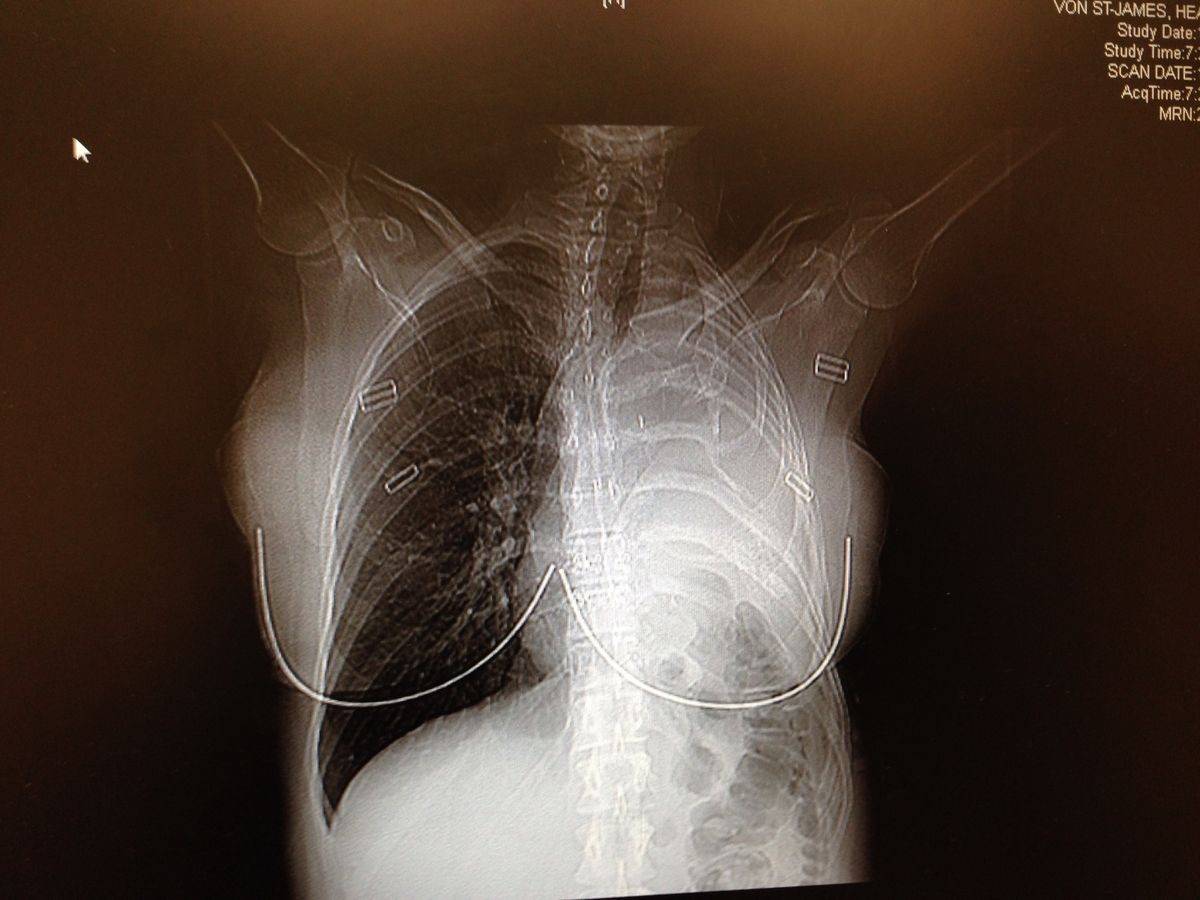

After giving birth by Caesarean section, the hairdresser went to see a doctor who put her through a CT scan, revealing a tumour near her lung.

Within two weeks, doctors diagnosed her with pleural mesothelioma, a rare and aggressive cancer linked to asbestos exposure. She was given around 15 months to live.